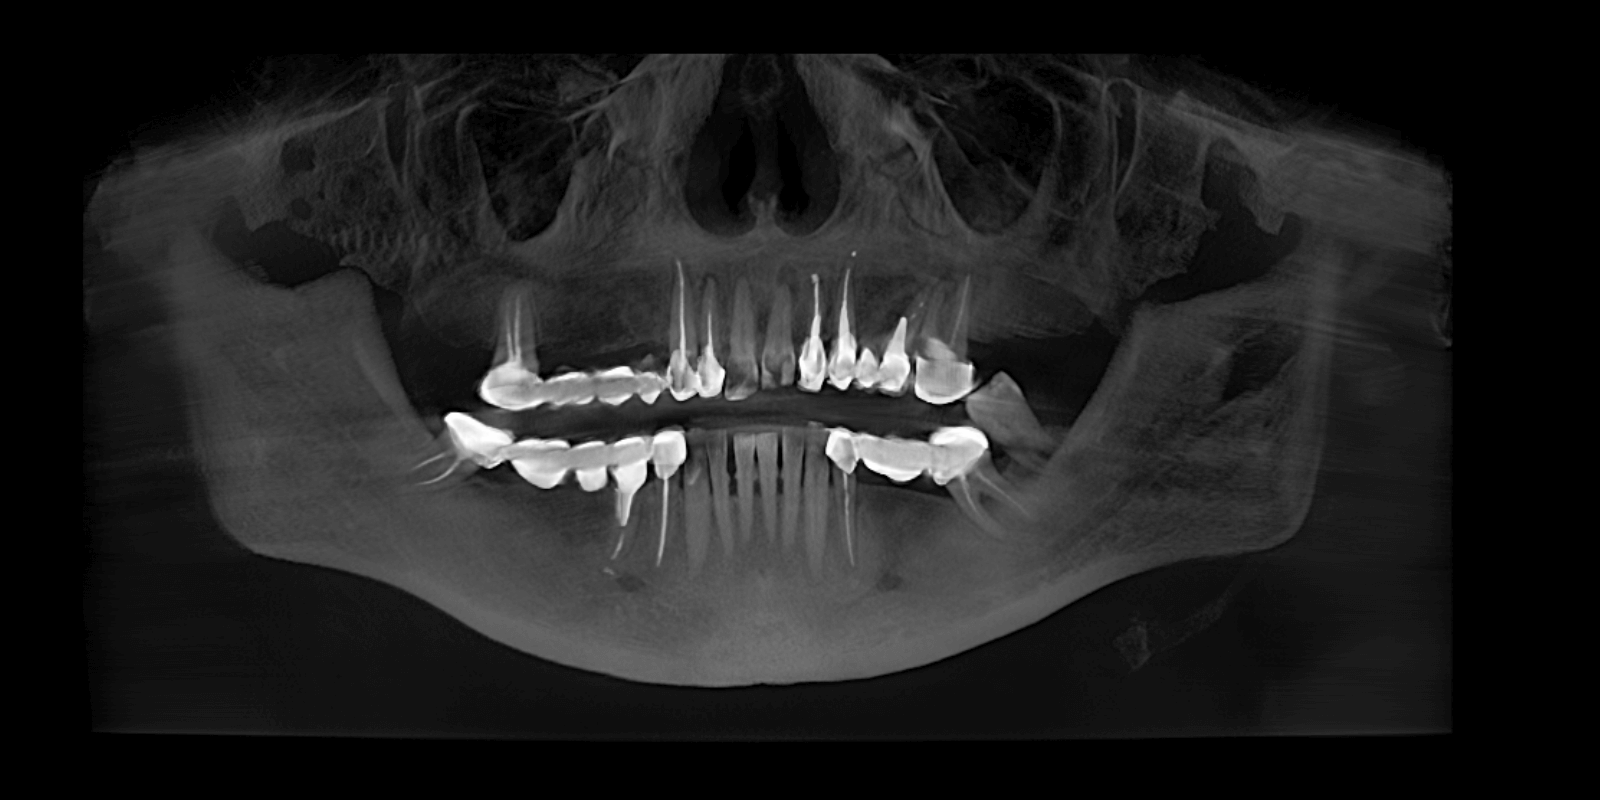

- Дополнительно, при изучении КТ, врач обнаружил гранулемы и кистогранулемы почти на всех опорных зубах под мостовидными конструкциями.

Провели КТ-исследование, на основе которого команда врачей составила план лечения, придерживаясь основных требований пациентки: "нужно сделать зубы быстро и красиво".